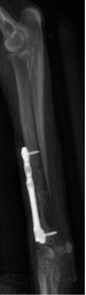

- Case 1 – Pomeranian with Radius/Ulna non-healing bone: Link to full case study

A 3.3 lb Pomeranian experienced 8 months of failed healing with only intermittent weight-bearing. After three PiezoWave treatments (1000 shocks, 0.191 mJ/mm²), callus formation was evident. After seven treatments, significant bone regeneration occurred, and within 3 months, the dog was fully weight-bearing with ongoing bone remodeling.